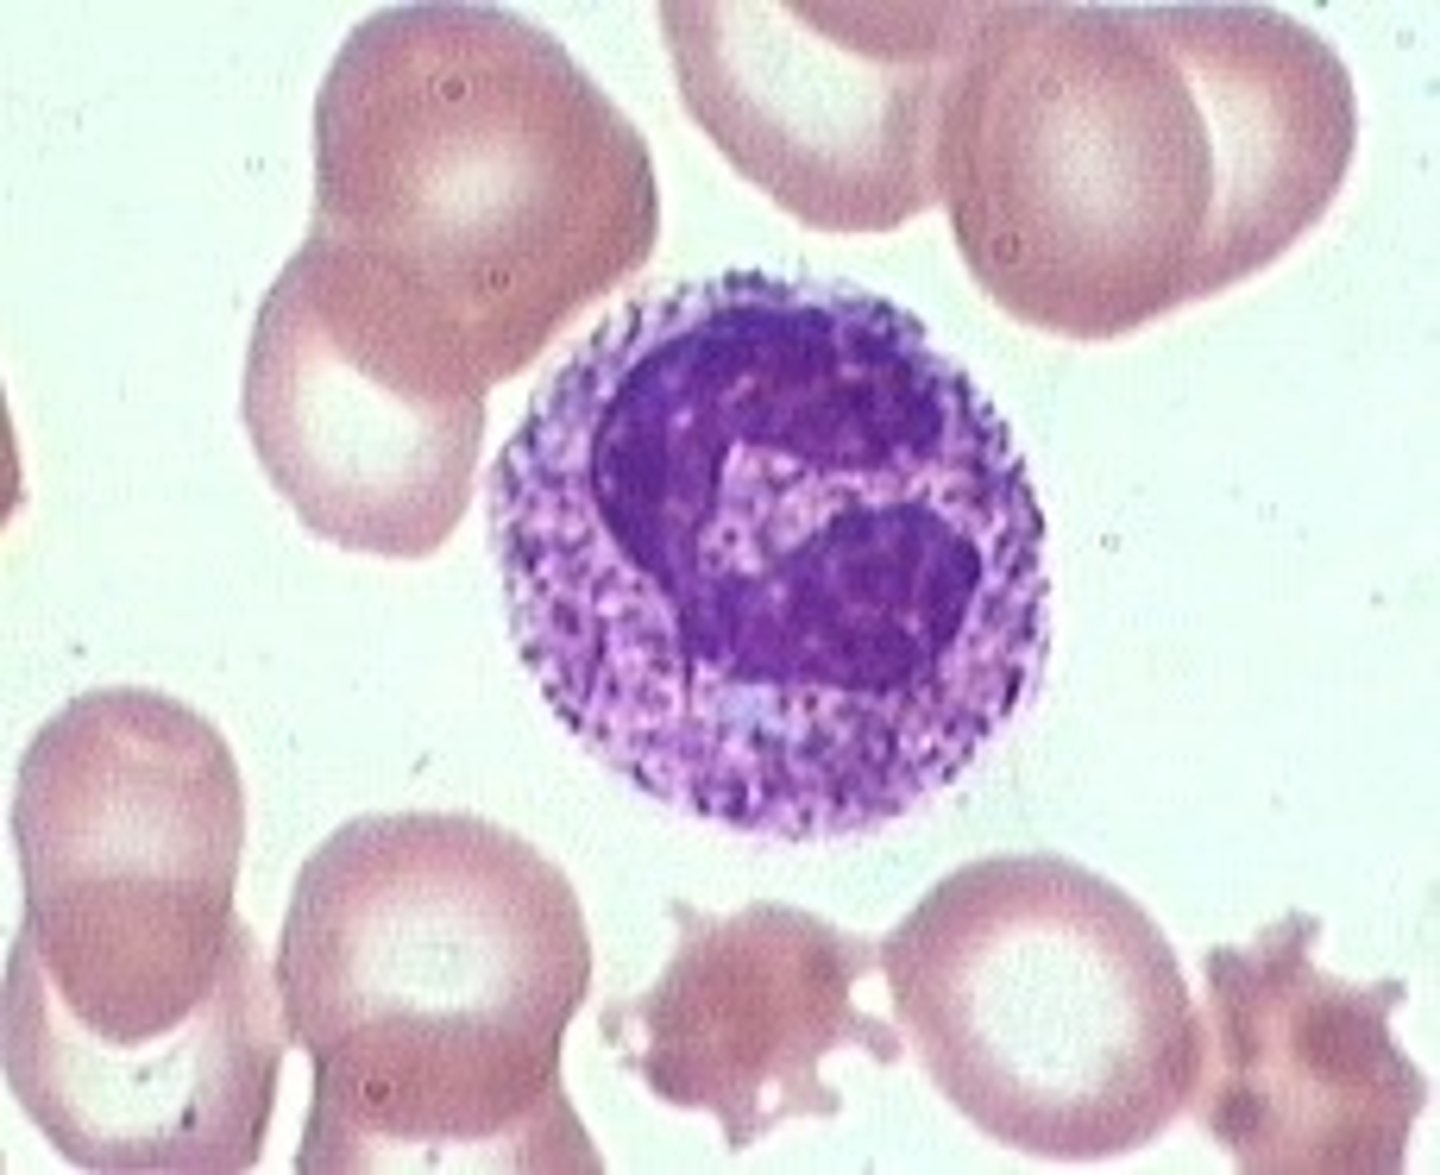

monocyte

MAMMAL

indented nucleus, basophilic cytoplasm